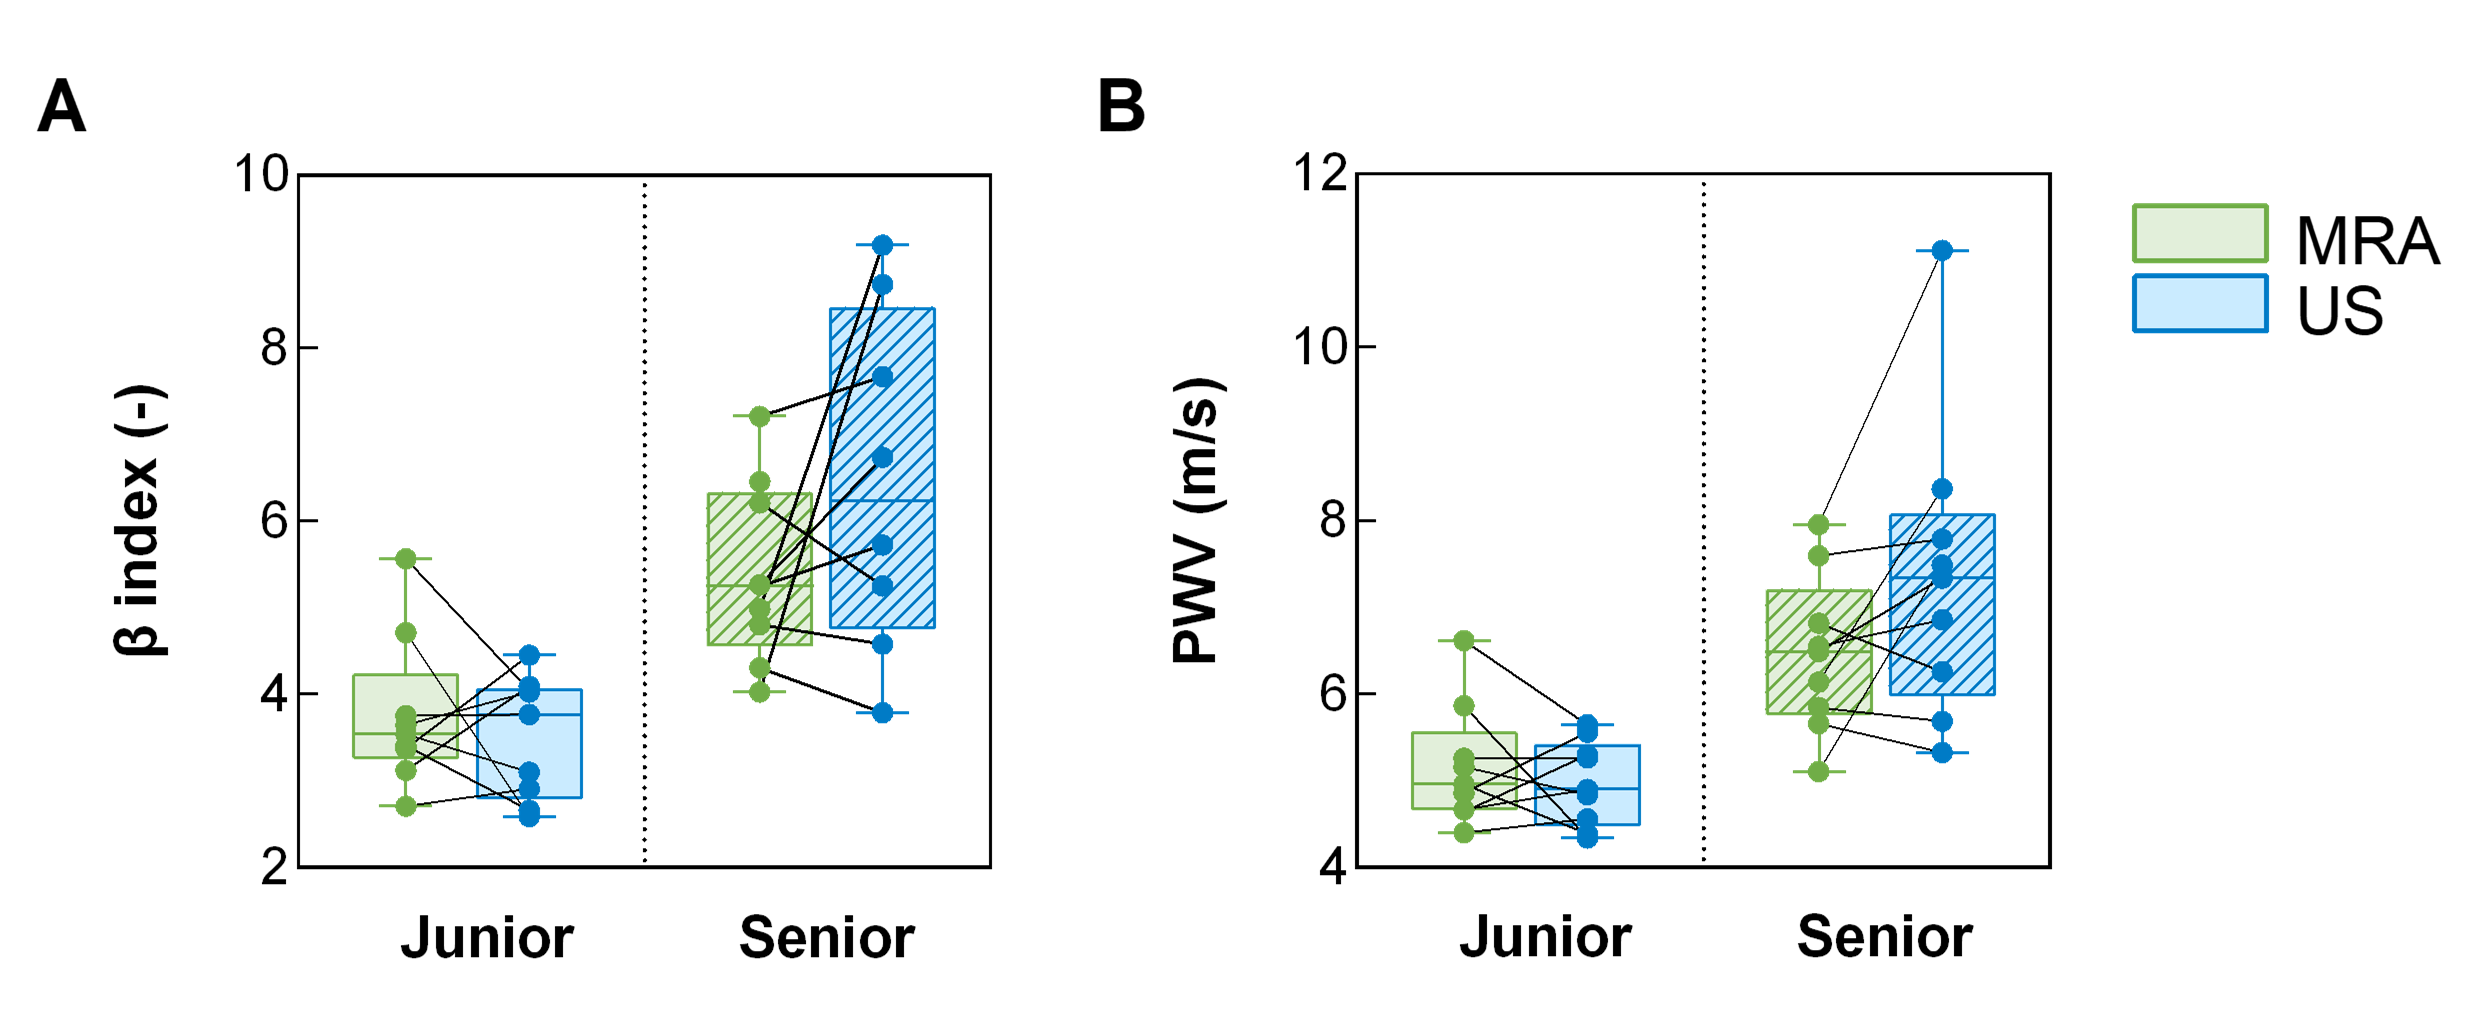

Methods: N=18 healthy volunteers were included and divided into two age subgroups: a junior cohort (n=9, 3F, 29±5Y) and a senior cohort (n=9, 6F, 61±7Y). Their CCA was scanned using both a US system (EPIQ Elite, Philips) (Fig. 1A) and a 3T MR scanner (PrismaFit, Siemens) using a free-running 3D radial GRE acquisition [3, 4] and slab-selective water excitation (flip angle 8º, pixel size (0.6mm)3, duration 10min). Both scans were performed twice to assess repeatability. MRI data were retrospectively sorted into 80 ms cardiac phases using pulse oximetry and reconstructed using compressed sensing [5] (Fig. 1B, 2).

CCA stiffness was evaluated as β=ln(Ps/Pd)/((Ds−Dd)/Dd), where P<sub>s and P<sub>d are the systolic and diastolic pressures (measured with an arm cuff), and Ds and Dd are the systolic and diastolic lumen diameters, measured manually for US (Fig. 1C,E) and semi-automatically for MRA (Fig. 1D,F). Local pulse wave velocity [6] was computed as PWV=√(β×Ps/2ρ), where ρ is the blood density.

Figure 1. Overview of US and MRI acquisition and analysis pipelines. (A) Acquisition of M-mode US images. (B) Continuous acquisition of MRA data using a segmented 3D golden-angle top-to-bottom phyllotaxis trajectory and k-space cardiac binning into N bins of 80 ms using the pulse oximeter signal. (C) Manual delineation of the interface between the vessel wall and the blood pool in the case of US. (D) Semiautomatic detection of the vessel wall using a full-width half-maximum (FWHM) approach. (E) For US, computation of the systolic and diastolic diameters by subtracting the previously delineated boundaries. (F) Detection of the systolic and diastolic diameters in the case of MRA.